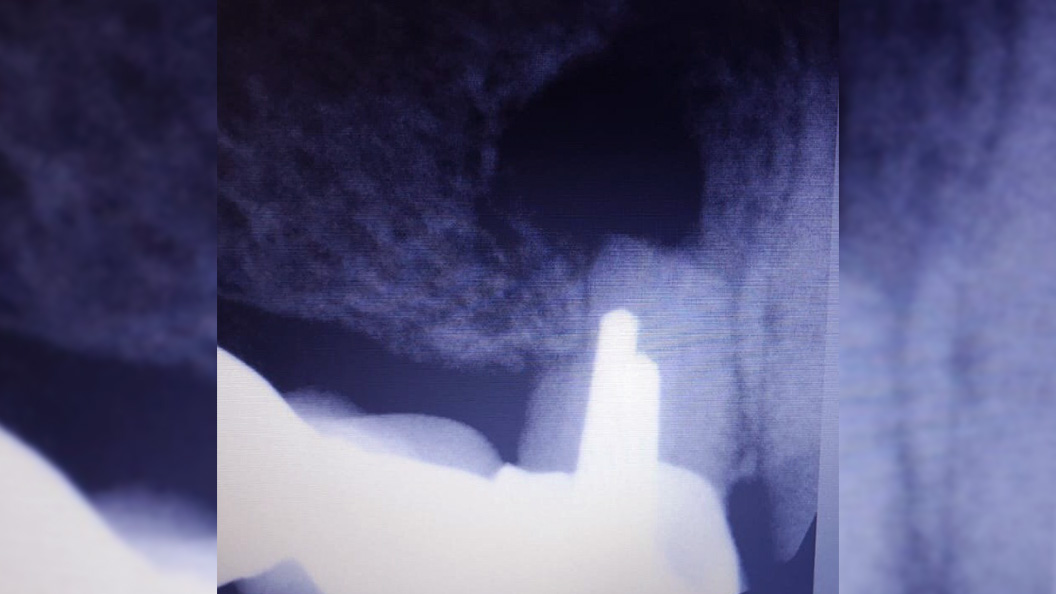

В нашу клинику обратился пациент с жалобами на резкую боль при накусывании справа вверху в области мостовидного протеза, который был установлен в другом лечебном учреждении.

После анализа сделанной рентгенограммы, врач-хирург Тарасов Денис Геннадьевич провёл резекцию верхушки корня зуба 1.4.

При неэффективности терапевтического лечения путём резекции верхушки корня одновременно с частью корня отсекается очаг воспаления в канале.